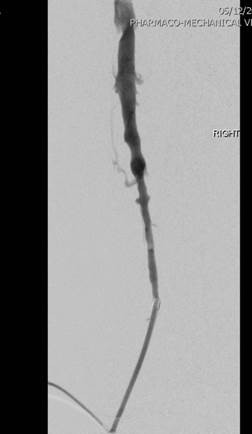

Venografía de la vena femoral tras trombectomía fármaco-mecánica (PMT) mediante la técnica Power Pulse Delivery (se usaron 15 ml de una solución de 50 mg de tPA  en 500 ml de solución salina natural) seguida por 2 pasadas con el catéter DVX de AngioJet.

Venografía en posición decúbito supino tras introducir 2 veces el catéter DVX de AngioJet. Vena ilíaca externa y vena femoral común del paciente. Estenosis severa de la vena ilíaca común.